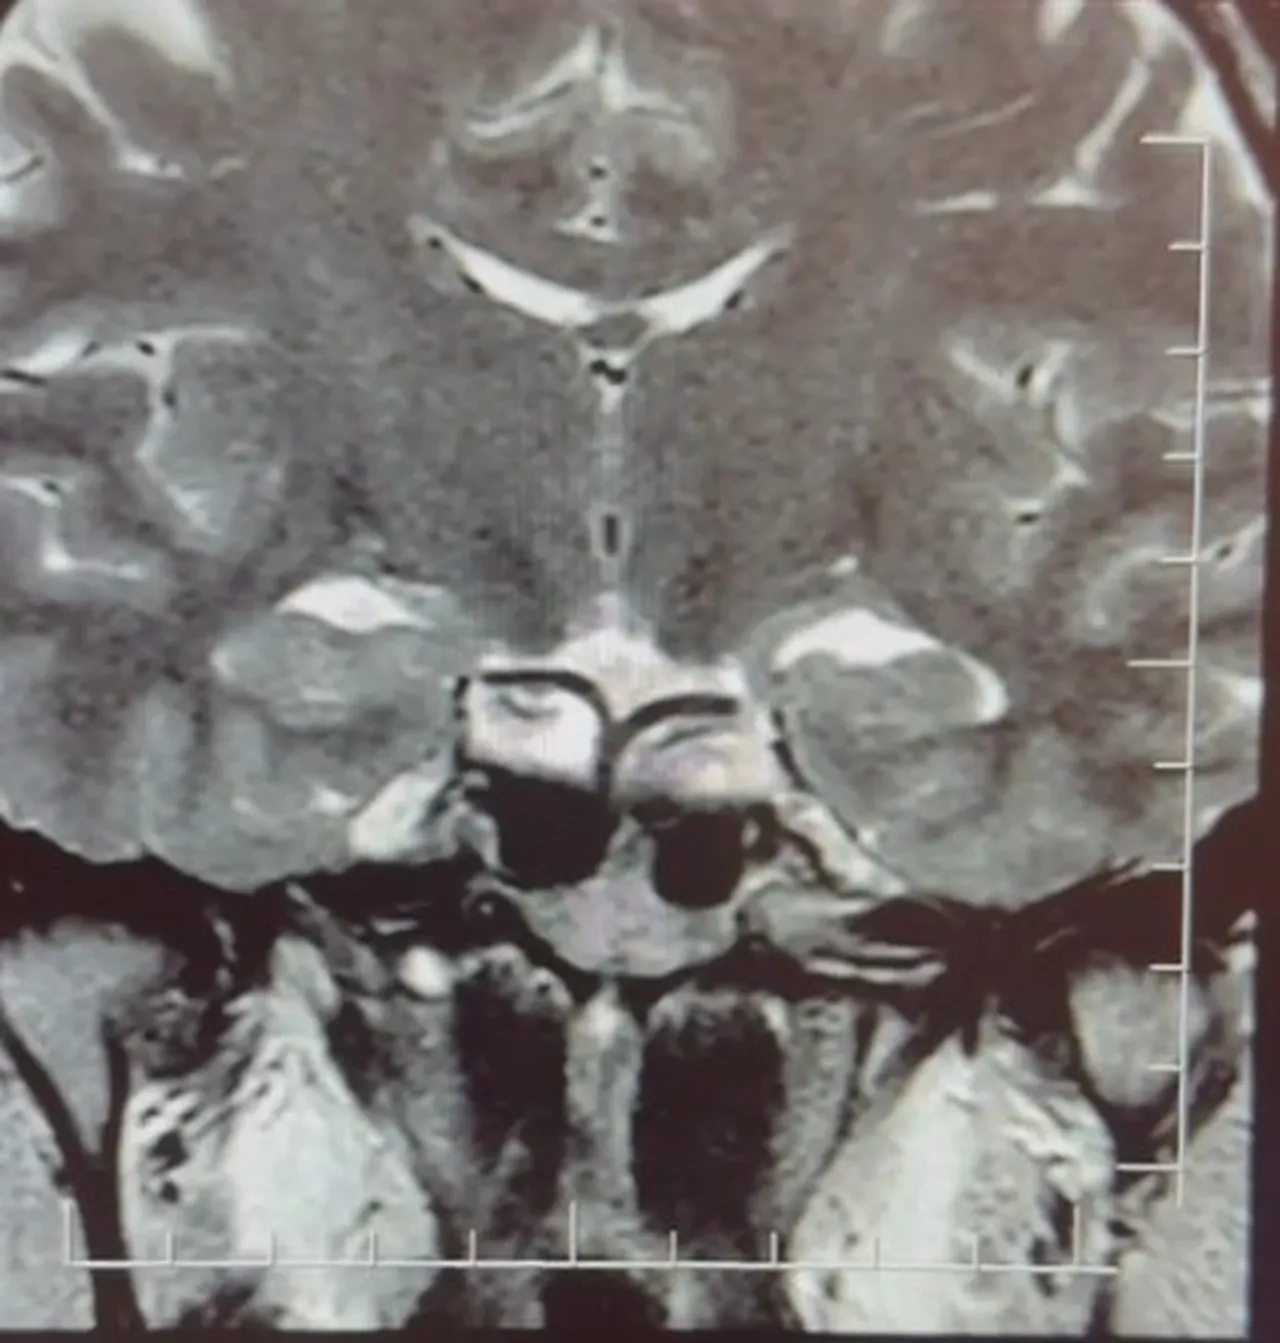

Yapılan ileri tetkiklerde hastaya hipofiz MR çekildiğini aktaran Çiftçoğlu, "MR sonucunda beynin hipofiz bölgesinde ‘prolaktinoma’ olarak adlandırılan bir tümör tespit ettik. Bu tümör, prolaktin hormonunun aşırı salgılanmasına neden oluyor. Genellikle iyi huylu olup ilaç tedavisiyle kontrol altına alınabiliyor" diye konuştu.

Gebelik belirtilerine benzer şikayetlerin farklı hastalıkların habercisi olabileceğine dikkat çeken Çiftçoğlu, "Prolaktin hormonu aslında beyinde hipofiz bezinden salgılanan ve süt salınımını sağlayan hormondur. Bunun yüksek olduğunu tespit ettikten sonra hastada hipofiz MR çektirdik. Çektiğimiz beyin MR'ında hastanın hipofiz dediğimiz bölgede kitleyi tümörü tespit ettik” dedi.